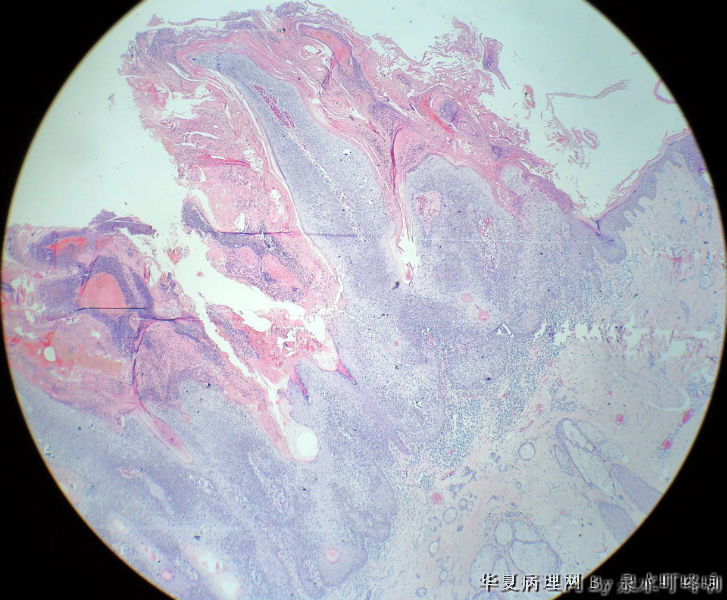

头皮肿物

120316,发现头皮肿物一月余。

大体:灰黑色带皮组织一块,于皮瓣中央可见一直径0.7厘米灰黑色肿物,高出皮表0.4厘米,表面带有毛发,

切面灰白,质中。

角化棘皮瘤

典型的脂溢性角化病,未见病毒感染的空泡细胞,不是寻常疣

倾向脂溢性角化病(上皮角平坦)。  未见病毒感染的空泡细胞,也未见明显上皮角辐辏现象不考虑寻常疣